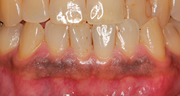

- でこぼこの歯肉のラインと白いセラミックの人工歯

- 歯肉が赤黒く腫れたまま、周りの歯や歯肉に調和しない

セラミックの人工歯が装着されています。